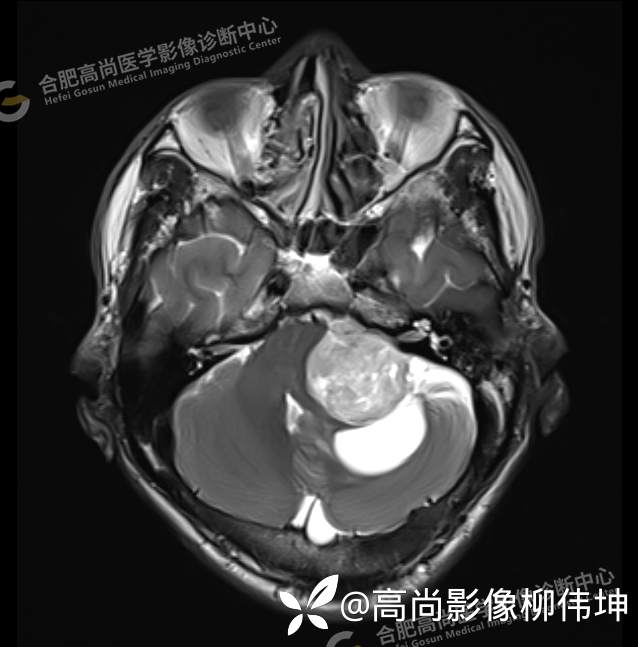

T2WI-FLAIR-tra

颅脑MRI平扫+增强示:双侧大脑半球对称,左侧桥小脑角区可见一团块状异常信号影,边界尚清,病灶与小脑幕宽基底附着呈“D”字征,上缘指状伸入幕缘上生长,病灶大小约43mmx42mmx36mm,其内信号不均,T1WI呈等低信号,T2WI呈混杂等高信号;FLAIR呈高信号,内可见条状低信号影,DWI呈稍高信号,ADC呈低信号,弥散轻度受限,病灶后方左侧小脑半球区可见一大小约33mmx16mm的弧形长T1长T2信号影,FLAIR呈低信号,其周围可见片状高信号影,相邻桥小脑角增宽。脑桥、小脑蚓部,小脑半球、第四脑室、环池受压变形,向右侧偏移,四脑室明显变窄,增强扫描病灶可见不均匀明显强化,邻近脑膜可见线样强化改变。其后方囊性灶未见异常强化。邻近骨质未见明显异常信号。左侧内听道显示正常;左侧中耳乳突内可见不规则性长T1长T2信号影。余脑实质内未见局灶性信号异常。双侧侧脑室及第三脑室体积增大,中线结构居中。矢状面示垂体形态大小正常,未见局灶性异常信号。

1.左侧桥小脑角区占位伴周围囊变,轻度梗阻性脑积水;考虑左小脑幕脑膜瘤。